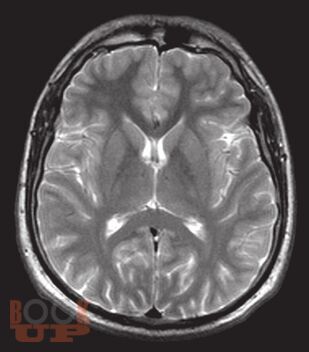

«Атлас нормальной анатомии магнитно-резонансной и компьютерной томографии головного мозга» посвящен актуальной проблеме нейроморфологии и краниологии — прижизненной макроскопической характеристике головного мозга и черепа с применением современных методов визуализации — магнитно-резонансной томографии и компьютерной томографии.

В Атласе представлены более 500 томограмм: магнитно-резонансные томограммы головного мозга, магнитно-резонансные ангиограммы головного мозга, магнитно-резонансные томограммы черепных нервов, компьютерные томограммы головного мозга, компьютерные ангиограммы сосудов головного мозга. Выполнена компьютерная реконструкция костей черепа, дана подробная информация об одном из сложнейших объектов черепа человека — височной кости.

Представленные томограммы могут заинтересовать специалистов в области магнитно-резонансной и компьютерной диагностики не только в качестве эквивалента нормы головного мозга, но и в пределах достаточно широкого диапазона индивидуальной анатомической нормы.